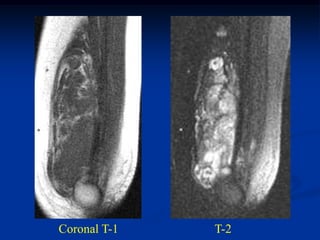

Case #1184.1              Lipoma               CT scan

51 year old male with soft painless mass in buttocks for 5 yrs

Axial T-1     T-2

Gad

Cor T-1         T-2

Sag gad

Case #1184.1 Lipoma CT scan 51 year old male with soft painless mass in buttocks for 5 yrs

• 50.

Axial T-1 T-2 Gad

• 51.

Cor T-1 T-2 Gad

• 52.

• 53.